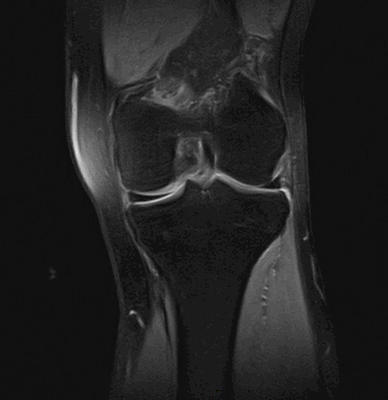

МРТ коленного сустава. Корональная Т2-взвешенаая МРТ. Нормальное состояние мениска после частичной менискэктомии.